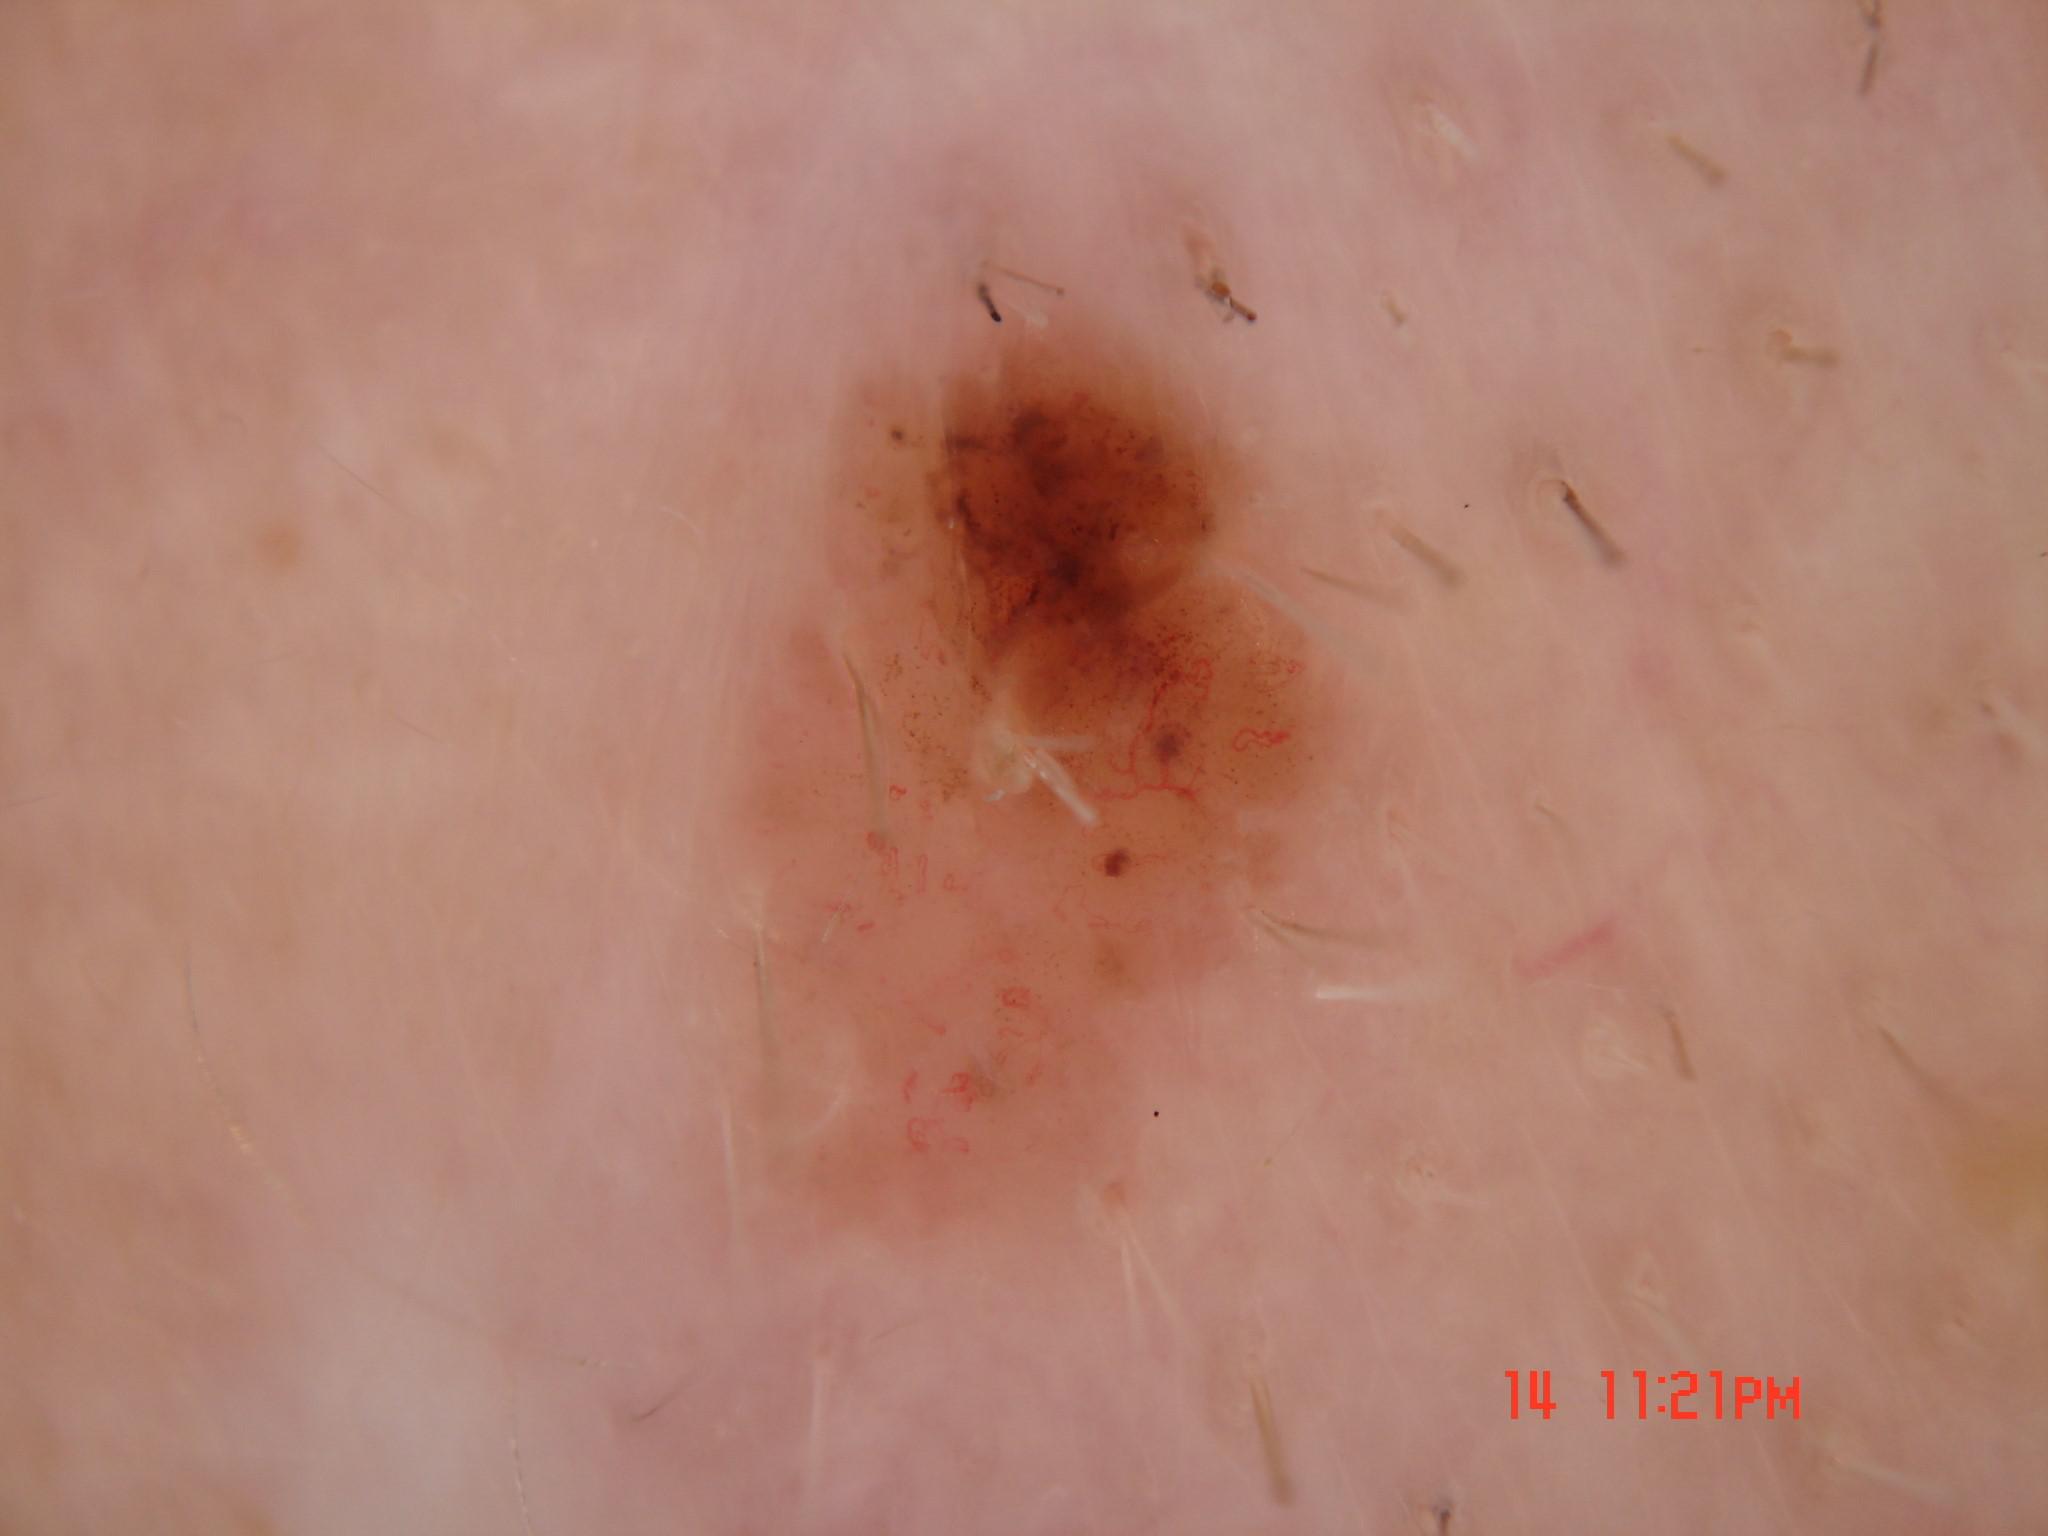

{

"age_approx": 85,

"anatom_site_general": "head/neck",

"concomitant_biopsy": true,

"dermoscopic_type": "contact non-polarized",

"diagnosis_1": "Malignant",

"diagnosis_2": "Malignant melanocytic proliferations (Melanoma)",

"diagnosis_3": "Melanoma in situ",

"diagnosis_confirm_type": "histopathology",

"family_hx_mm": false,

"image_type": "dermoscopic",

"mel_thick_mm": "0.00",

"melanocytic": true,

"patient_id": "IP_0202761",

"personal_hx_mm": false,

"sex": "male"

}